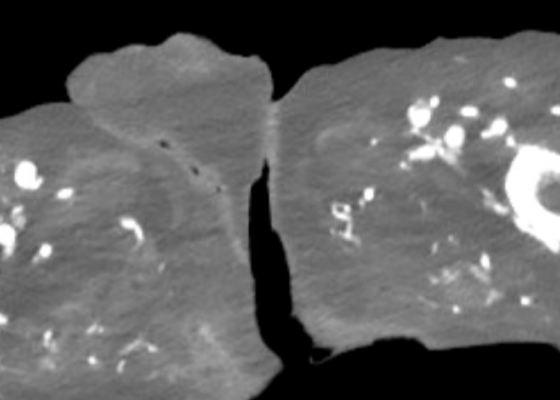

DOI: https://doi.org/10.5070/M5.52203A computed tomography (CT) scan of the abdomen and pelvis was significant for scrotal fluid and punctate gas locules (red arrow) without discrete evidence of invasion into the adjacent soft tissues, suspicious for Fournier’s gangrene. There was also fluid collection centered around the seminal vesicles suggestive of an abscess.